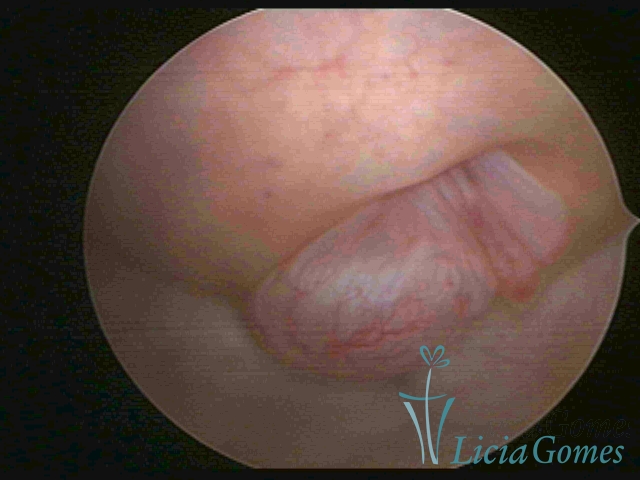

ENDOCERVICAL POLYPS

Benign tumors resulting from the reactive focal proliferation to inflammatory processes or hyperestrogenism situations, which may be sessile (with a large implantation) or stalked.